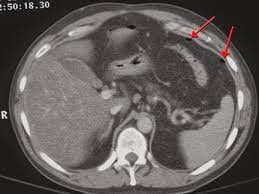

Cùng với sự tiến bộ của công nghệ, chụp cắt lớp vi tính (Chụp CT) gan không chỉ đơn thuần dừng lại ở việc khảo sát hình ảnh và cấu trúc của nhu mô gan trong các tổn thương gan mà còn cho phép dựng hình đường mật của người bệnh giúp ích cho việc chẩn đoán các bệnh lý gan mật. Hệ thống đường mật trong và ngoài gan đều có thể được khảo sát và tái tạo hình ảnh cấu trúc một cách chân thật. Phương pháp này có khả năng bổ sung cho siêu âm gan mật trong những trường hợp tổn thương nhỏ, phức tạp và đánh giá tổng quan cấu trúc gan và hệ thống đường mật đi kèm, đặc biệt trong các bệnh lý tắc nghẽn lưu thông đường mật như u đường mật, sỏi mật.

- Tiến hành chụp: khi đã cố định người bệnh ở tư thế nằm ngửa, hai tay để cao ngang đầu, tiến hành bộc lộ vùng khảo sát từ giữa xương ức đến hai xương cánh chậu. Chụp cắt lớp vi tính gan có dựng hình đường mật ở các thì trước khi bơm thuốc thì động mạch tương ứng với khoảng 20 giây kể từ thời điểm bơm thuốc và thì tĩnh mạch tương ứng với 60 giây sau khi bơm thuốc. Hình ảnh được tái tạo tương ứng với cài đặt của từng máy, phụ thuộc vào độ phân giải của máy, độ dày của các lát cắt, khoảng cách giữa chúng, kỹ thuật chụp, tư thế Bất động của người bệnh ... Một hình ảnh đẹp khi hiển thị rõ các chi tiết liên quan đến cấu trúc, hình dạng và mối tương quan về vị trí giải phẫu của gan và hệ thống đường mật trong và ngoài gan. Các tổn thương gan, tổn thương hệ đường mật, biến chứng chèn ép của chúng lên các cơ quan xung quanh cũng cần được đánh giá một cách chi tiết và rõ ràng.